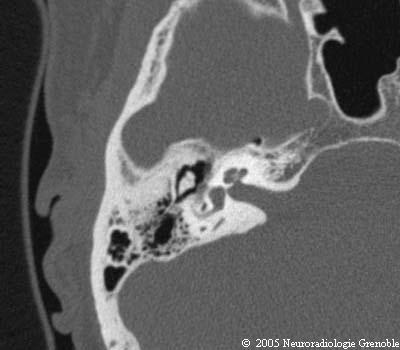

Radioanatomie TDM du rocher normal

Conduit auditif interne

Cochlée

Canal semi circulaire postérieur

Enclume (corps)

Antre

Marteau (tête)

Vestibule

Acqueduc du vestibule